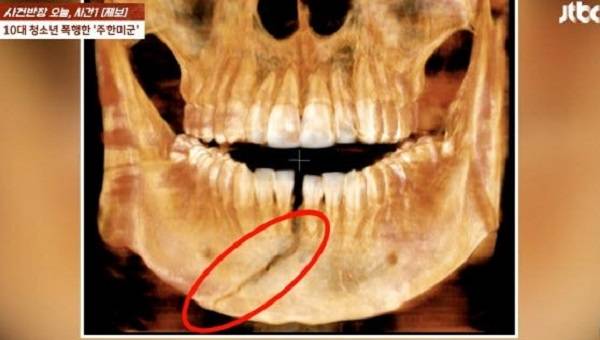

A씨는 지난 17일 0시30분쯤 평택시 평택역 인근의 한 거리에서 10대 B군의 얼굴을 주먹으로 때려 다치게 한 혐의를 받는다. B군은 턱뼈가 부서지는 등의 중상을 입었다.

B군의 아버지는 19일 JTBC ‘사건반장’에 사건을 제보해 공론화했다. 그는 “의사가 ‘사람이 때렸다는 생각이 안 들었다’고 했다. 사람이 주먹으로 때렸을 때 이 정도 관절 나가는 건 성형외과 의사로 지내면서 처음 보는 일(이라고 하더라)”고 말했다.

이어 “(아들은) 입안에 보철을 착용하고 고정한 상태로 8주 동안 있어야 한다”며 “워낙 (피해) 정도가 심해서 평생 후유 장애가 남을 수도 있다고 한다”고 전했다.